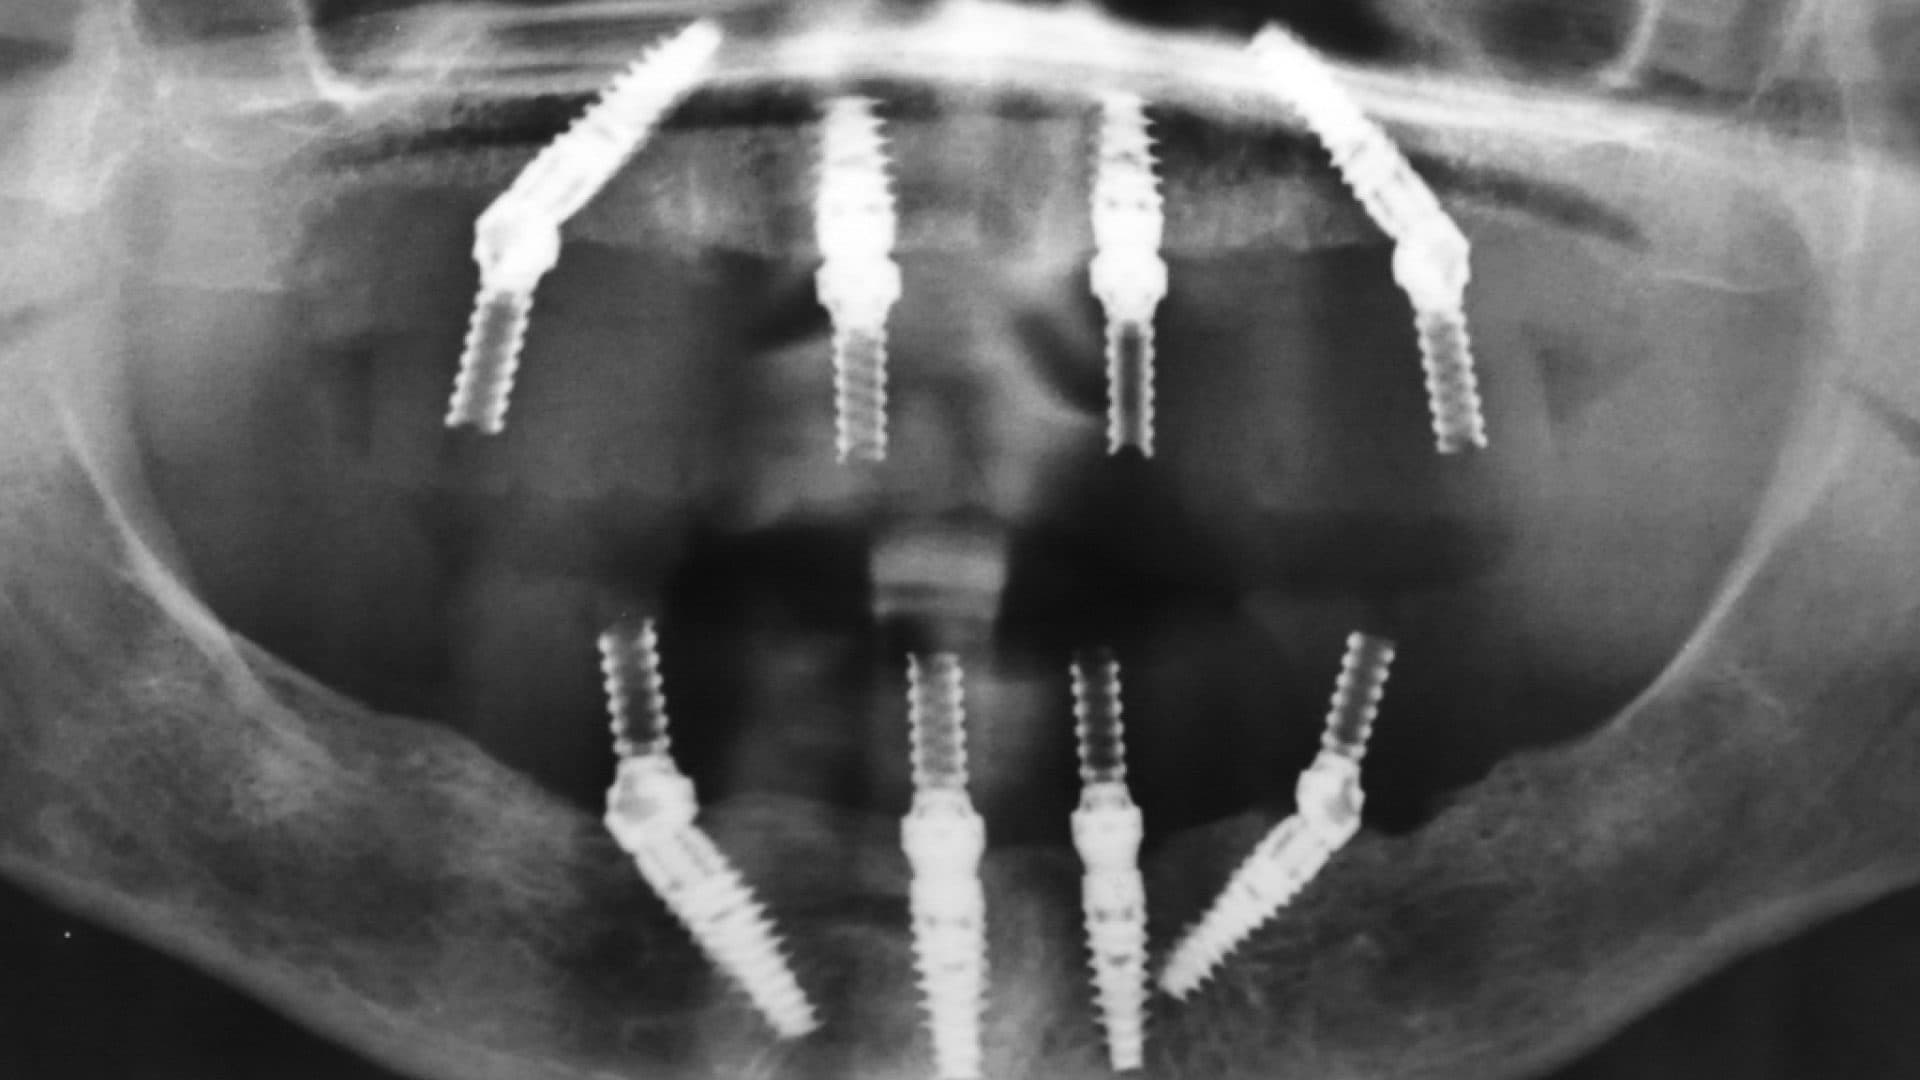

iii. Alignment on x-rays: there should be even spread, rigid connection between the implants, good bone levels, and the height of the prosthesis should be at least as tall as the shortest fixture (See pictures).

Examples Of Poor Standards